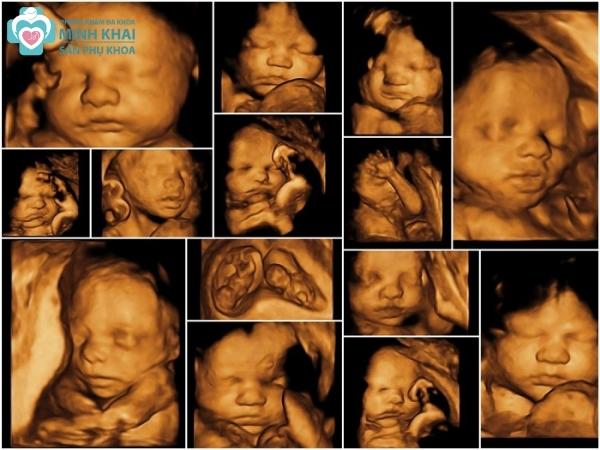

Siêu âm thai 3D cho phép thấy được hình ảnh chụp thật 3 chiều của em bé chứ không phải chỉ là những mặt cắt như 2D. Không chỉ vậy hình ảnh 3D còn được chụp với các góc độ khác nhau. Nó cho thấy rõ được toàn bộ cấu trúc thai nhi chi tiết đến từng đường nét cũng như nội soi rõ các mô nội tạng, tim, hệ mạch máu,...

Vậy nên công cụ siêu âm 3D rất đắc lực trong việc phát hiện bất thường, dị tật bẩm sinh của thai nhi. Chúng cho phép chẩn đoán chính xác các vấn đề về não nhờ phân tích các “điểm mềm” tồn tại trong hộp sọ của thai nhi ở tuần thứ 15 đến 17 thai kỳ.

Siêu âm thai 4D

Siêu âm thai 4D phản ánh được hình thái thai nhi bằng các ảnh động nên rất ba mẹ có thể quan sát con rất có thần thái và sống động. Thiết bị 4D có thể bắt trọn được những khoảnh khắc đáng yêu của bé yêu như ngáp ngủ, đưa tay dụi mặt, đạp chân,... Nhờ vậy bạn có thể theo dõi kỹ sự phát triển của con có ổn định hay không và đánh giá rủi ro tiềm ẩn trong thai kỳ để sớm tìm ra hướng giải quyết tốt nhất.

Siêu âm 3D, 4D, 5D cũng giúp bạn theo dõi được bức ảnh tổng thể và chi tiết các cơ quan của thai nhi. Tuy nhiên chất lượng hình ảnh của chúng sẽ rõ ràng và sắc nét hơn siêu âm 2D gấp nhiều lần. Thậm chí siêu âm 4D, 5D còn có thể phản ánh cử động của thai nhi rõ ràng, chân thật qua các bức ảnh động.